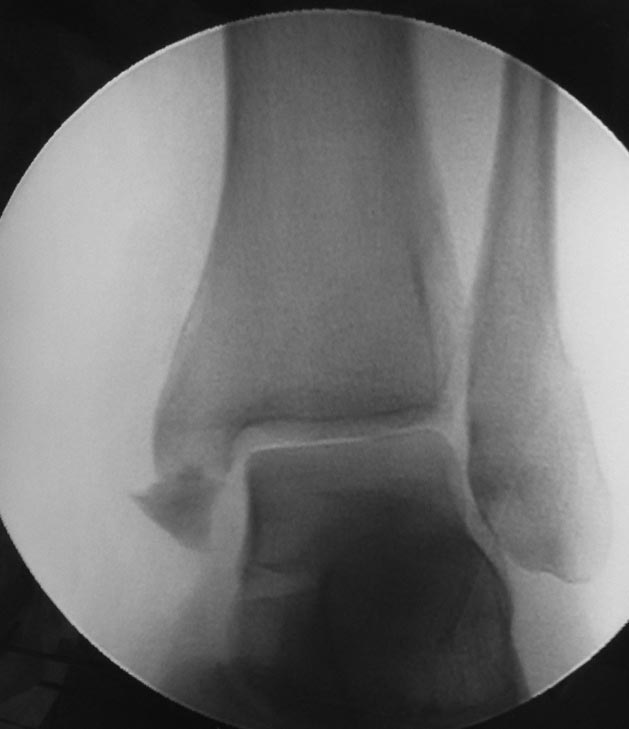

Немедленно удалить "позиционный" винт, который работает как болт-стяжка и синдесмоз явно перетянут. Учитывая форму тарана, иной установки стопы ожидать сложно, оптимально спицы заменить на винт.

Отправлял до- и послеоперационные снимки, но почему-то проявились только послеоперационные. Досылаю остальные.

Такое впечатление, Максим, что Вы куда-то бежали и написали ответ, не успев перевести дух. Прочитайте, пожалуйста, внимательно вопросы. Они не о качестве остеосинтеза, который я не планировал обсуждать. Но если уж на то пошло, как можно говорить о перетянутом синдесмозе, не видя другой ноги? Сначала я ввел этот винт даже глубже, но затем отпустил, ориентируясь на здоровый голеностоп. Пациентка к моменту выписки безболезненно и свободно двигала стопой. Тыльное сгибание оперированной стопы практически сравнялось с противоположной. Обычно я выписываю таких пациентов на следующий день или через день после операции. Эту пациентку задержал на 4 дня, чтобы с ней позанимался специалист по ЛФК, учитывая контрактуру трицепсов. А фиксировать такие маленькие фрагменты внутренней лодыжки винтом привычки не имею из-за неизбежного повреждения прикрепляющейся к лодыжке связки. Спицы, как Вы видите, через связку не проходят.

как можно перетянуть таким винтом синдесмоз,ладно обычным кортикальным,а этим....+винт вообще недотянут,головка винта выпирает.подтянутые вровень,а этот выпирает.не?

С винтом тут понятно. Пластина блокируемая. Винты ввинчены в нее заподлицо. А синдесмозный введен под углом. Это синтезовская пластина. Угол введения только один, прямой. Поэтому головка синдесмозного винта и не могла погрузиться полностью. Но синдесмоз не перетянут, это правда.

Я поддержу Максима. Не нравиться мне остеосинтез! Имплант модный, современный, репозиция наружной лодыжки идеальная, суставная щель какаду-то равномерная.....Какбуд-то.

Про репозицию: Медиальная лодыжка чуть не дорепонированв, реально медиальное щель уже, чем в норме. Про синдсмоз по этим проекциям судить нельзя. Сделайте КТ - можете удивиться тому, что найдете.

Про остеосинтез: перелом наружной лодыжки простой, отремонтирован идеально, а где стягивающий винт? Межберцовый винт: в его качестве locking had screw, а не обычный кортикальный? В каких руководствах или статьях есть такая рекомендация? Этот винт проведен через сам синдесмоз на 1 см проксимальнее сустава - а это в соответствии с какими рекомендациями? Вроде рекомендуют повыше немного?

Перед введением позиционного винта берцовые кости сжал пальцами одной руки. Спокойно, без мата. Через противоположный кортикал винт провел из-за того, что после остесинтеза наружной лодыжки щель синдесмоза все-таки оставалась расширенной и легко сжималась пальцами руки. Теоретически это может происходить из-за неточной репозиции наружной лодыжки. Но, насколько я видел во время операции - репозиция была точной. И еще раз повторю, что после проведения винта через противоположный кортикал, вывинтил его обратно на 2-3 оборота, ориентируясь под ЭОПом на здоровую конечность.

Данный перелом относится к Weber B 2, косой перелом наружной лодыжки с разрывом переднего отдела синдесмоза. Правильно установленная пластина отрепонирует перелом и синдесмоз! Небольшие разрывы синдесмоза можно оставить без фиксации, но этот вопрос преференции хирурга. Чтобы не выступал на пластине позиционный винт можно провести спереди или сзади пластины, и для доказательства надо делать стресс тест, и желательно сохранить снимки!